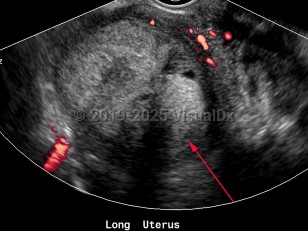

Endometrial carcinoma

Endometrial carcinomas are more common in White women and more likely to develop after menopause. The highest incidence worldwide is seen in the United States.

Most commonly, endometrial carcinoma develops in conditions that expose the uterus to estrogen, either for very prolonged periods of time, without opposing progesterone, or both. As such, obesity, polycystic ovarian syndrome (PCOS), diabetes mellitus type 1 and type 2, anovulation, nulliparity, tamoxifen use (in postmenopausal women), prolonged hormone replacement therapy with estrogen alone, and early menarche or late menopause are all variably potent risk factors for endometrial carcinoma.